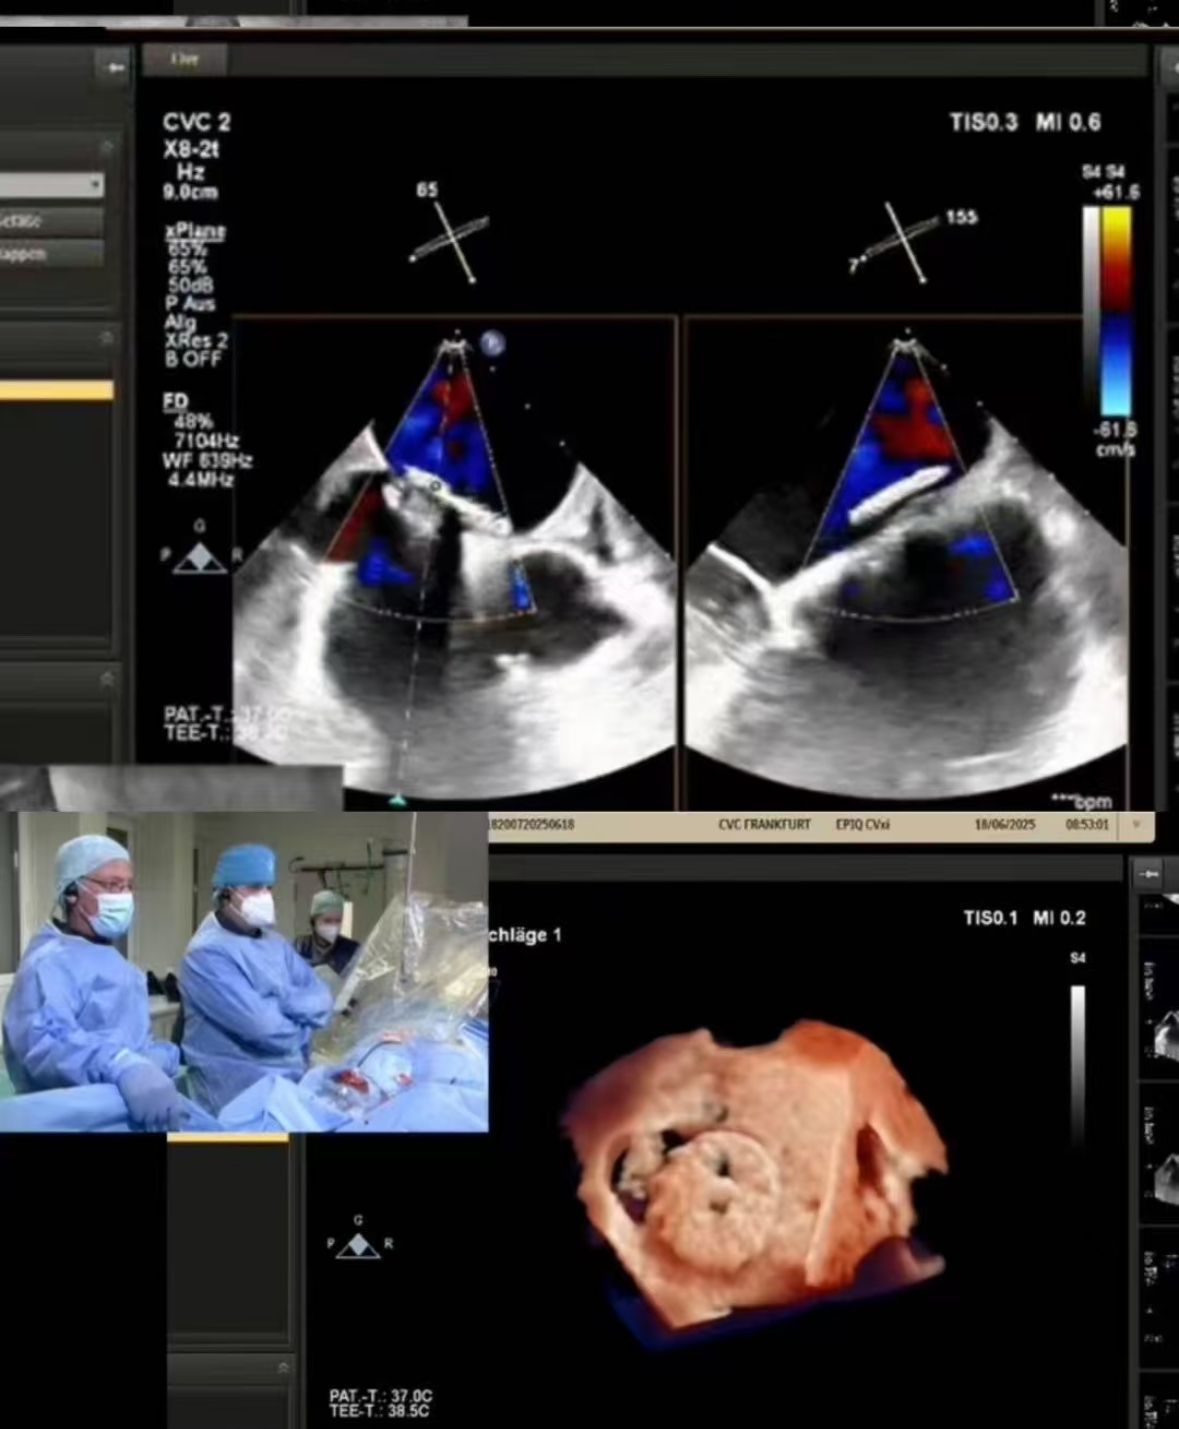

Thrilled to showcase our MemoSorb PFO Occluder – the world's first absorbable device (degrades to water & CO₂ within 1 year) – during a live broadcast from the Blue Room at CSI Frankfurt!

Мы транслировали комплексное закрытие PFO, выполненное в CVC Frankfurt на 60-летней пациентке с:

1. Повторяющиеся эмболические инсульты (2014, 2021)

2. Тяжелая аллергия на никель (противопоказание для металлических приборов)

3. Остаточный шунт после предыдущего закрытия

2. Точное закрытие: идеальное развертывание в сложной анатомии с визуализацией в реальном времени (туннельная фенестрация PFO).